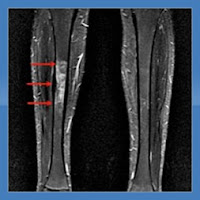

São necessários para confirmação diagnóstica os métodos como ressonância magnética (RM- figura 1) ou cintilografia óssea, que apresentam uma boa sensibilidade. A cintilografia óssea detecta a fase inicial da patologia, cerca de 95% dos casos em menos de 24h da lesão.

(figura 1)- Ft estresse da tíbia. As setas em vermelho mostram a área de micro-fraturas